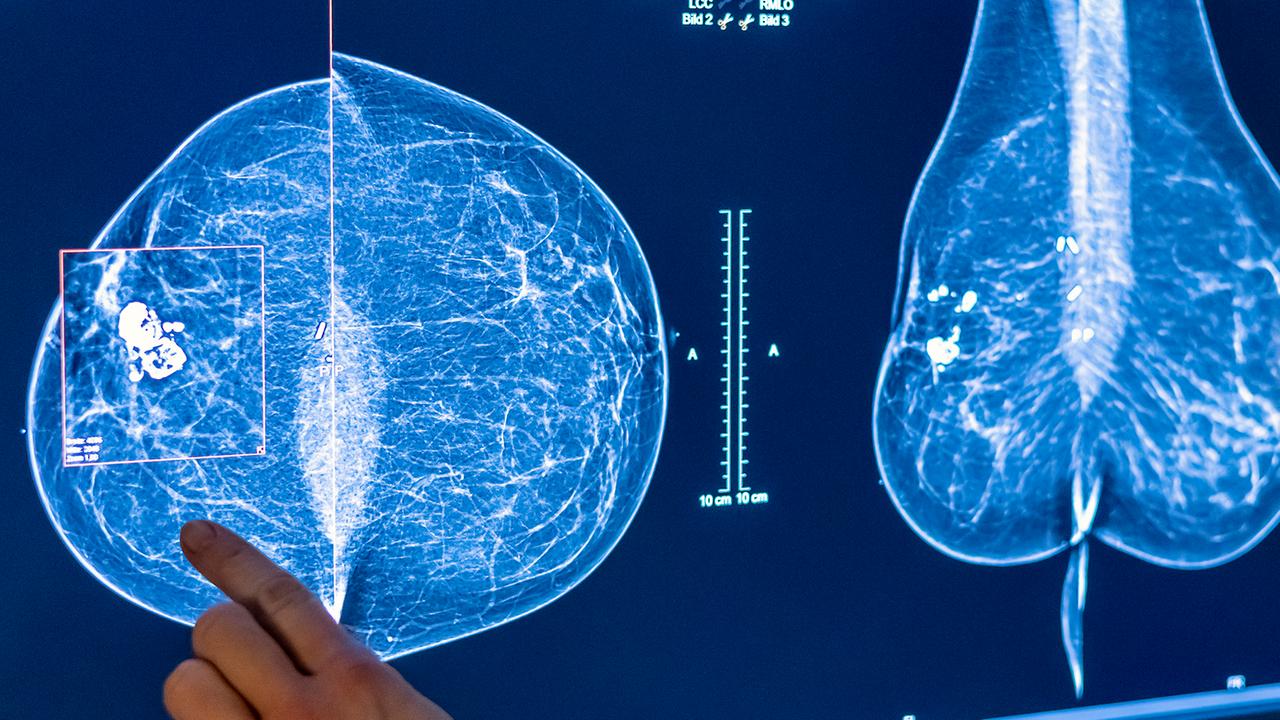

Bessere Krebsdiagnose und -therapie dank KI

In der Krebsmedizin gewinnt Künstliche Intelligenz gerade enorm an Bedeutung. Doch es gibt noch Probleme - zum Beispiel, wenn es um die Zusammenarbeit von Mensch und KI geht. Von Frank Wittig.